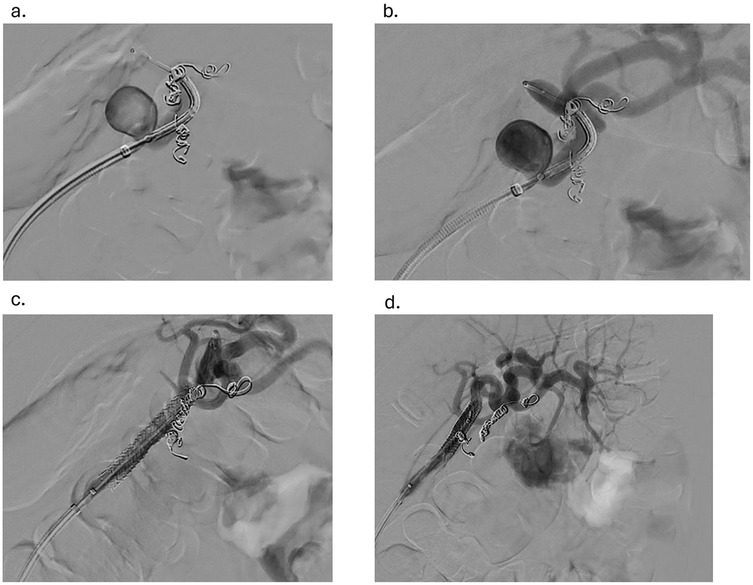

Under sterile conditions, the right femoral artery was accessed using the modified Seldinger technique, and a 5 French vascular sheath was inserted. The splenic artery was selected using a 5-French Cobra catheter and a 0.035-inch hydrophilic Glidewire. A contrast run at the proximal splenic artery showed a large splenic artery aneurysm arising at the bifurcation of major branches. The vascular sheath was exchanged for a larger flexor sheath, which was advanced into the distal splenic artery just proximal to the splenic artery aneurysm. Two minor branches were identified as arising from the aneurysmal sac (Figure 1a). These were individually selected with a microcatheter and embolized with seven Cook Medical® Micronester® embolization coils to prevent backfilling of the aneurysm(Figures 1b,c). Following coil embolization, the remaining dominant branch was selected, and the flexor sheath was advanced across the aneurysm neck, confirming adequate exclusion and distal flow. Then a single balloon-mounted 7 mm Bentley® BeGraft® covered stent was advanced and deployed across the aneurysm neck and unsheathed by slowly retracting the flexor sheath and confirming the appropriate desired location with sequential arteriography (Figures 2a–c). Post-stent deployment angiography showed complete exclusion of the aneurysmal sac with preserved patent flow into the dominant splenic artery branch (Figure 2d). There were no intraoperative and acute postoperative complications. The patient was placed on dual antiplatelet therapy composed of 81 mg aspirin and 75 mg clopidogrel per day. In brief, successful isolation of a large proximal splenic artery aneurysm and preservation of patency of the dominant splenic artery branch were performed by using a covered stent and coiling of minor branches to prevent aneurysm backfilling.

Figure 2. (a) advancement of the balloon-mounted 7 mm covered stent across the aneurysm (b) confirmation of the desired location of the endoprosthesis with sequential arteriography (c) withdrawal of the flexor sheath to the desired location and the stent graft deployed (d) angiogram showing the aneurysm post-coiling of branches and stent graft placement.